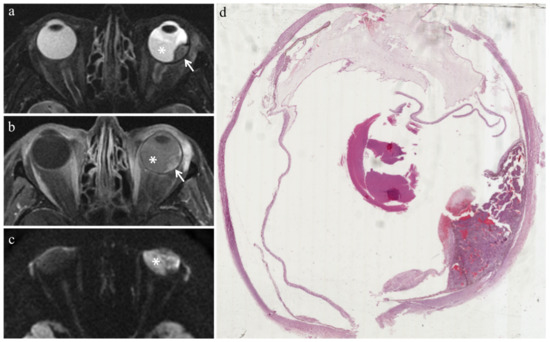

| MR Finding | T2 | T1 | Gd-T1 | DWI |

|---|---|---|---|---|

| Radiation-induced necrosis | ![]() Low signal | ![]() High signal | ![]() No enhancement | ![]() Low signal |

| Fibrosis | ![]() Low signal | ![]() Intermediate signal | ![]() Moderate enhancement | ![]() Low signal |

| Viable tumor tissue, pigmented melanoma | ![]() Low signal | ![]() High signal | ![]() Enhancement of viable tissue | ![]() High signal |

| Viable tumor tissue, poorly pigmented melanoma | ![]() Intermediate signal | ![]() Intermediate signal | ![]() Enhancement of viable tissue | ![]() High signal |

low signal;

intermediate signal;

high signal;

no enhancement;

enhancement of the viable tissue.| MR Finding | T2 | T1 | Gd-T1 | DWI |